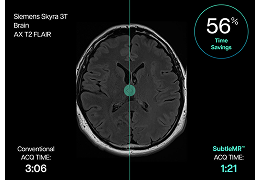

Eclipse 成像智能功能提供强大的处理能力和最佳质量的影像,同时减少质量错误并提高剂量效率。

凭借 AI、专有算法和先进的影像处理能力,提供出色的影像质量和无与伦比的诊断信心。

与标准影像处理相比,智能降噪功能可使客户降低辐射剂量,而不会损失影像质量。这在新生儿和儿科成像中尤其重要,在这种情况下以尽可能低的剂量成像至关重要。